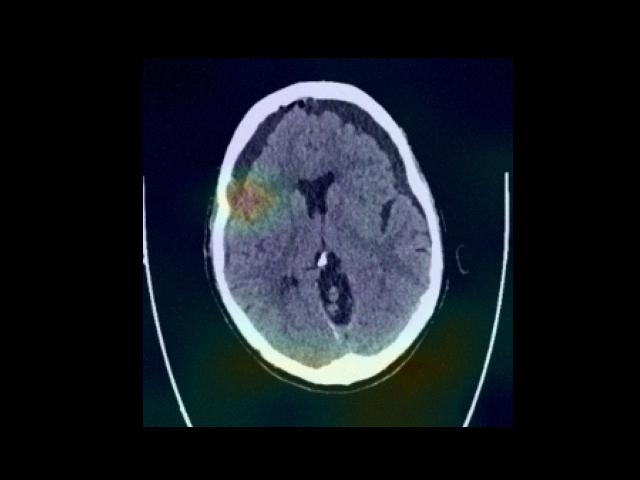

Sample Gallery